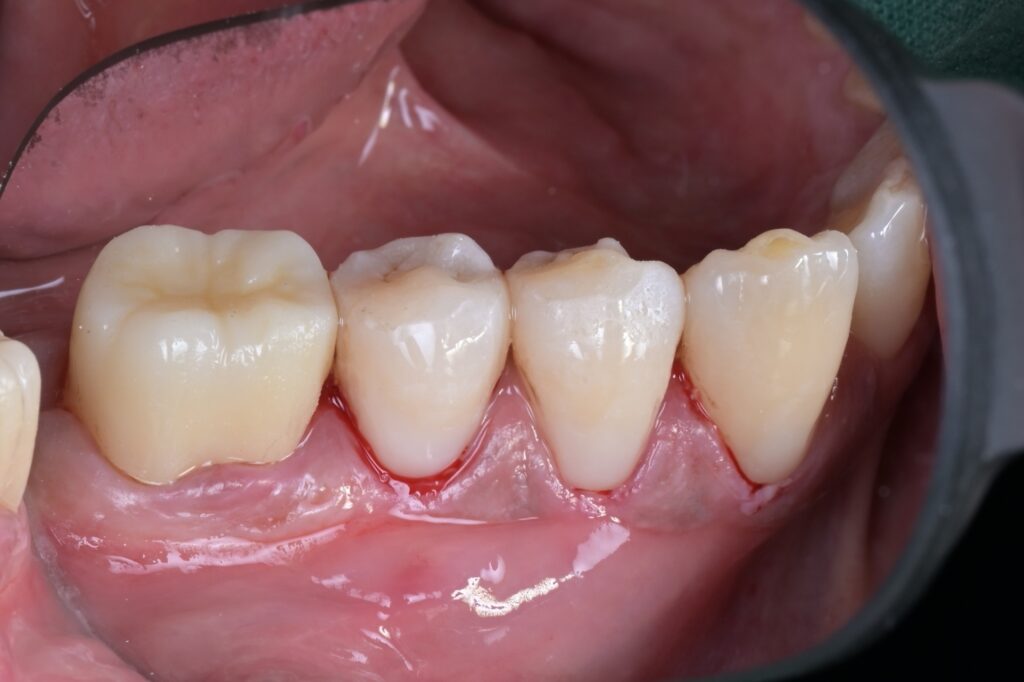

모든 과정을 마치고 러버댐과 클램프를 제거한 직후의 모습입니다.

잇몸 라인을 따라 자연스럽게 치료된 모습, 보이시나요? 잇몸이 살짝 눌려있지만, 이는 하루 이틀이면 금방 가라앉습니다. 중요한 것은 치아와 레진 사이에 틈이 전혀 없다는 점입니다.